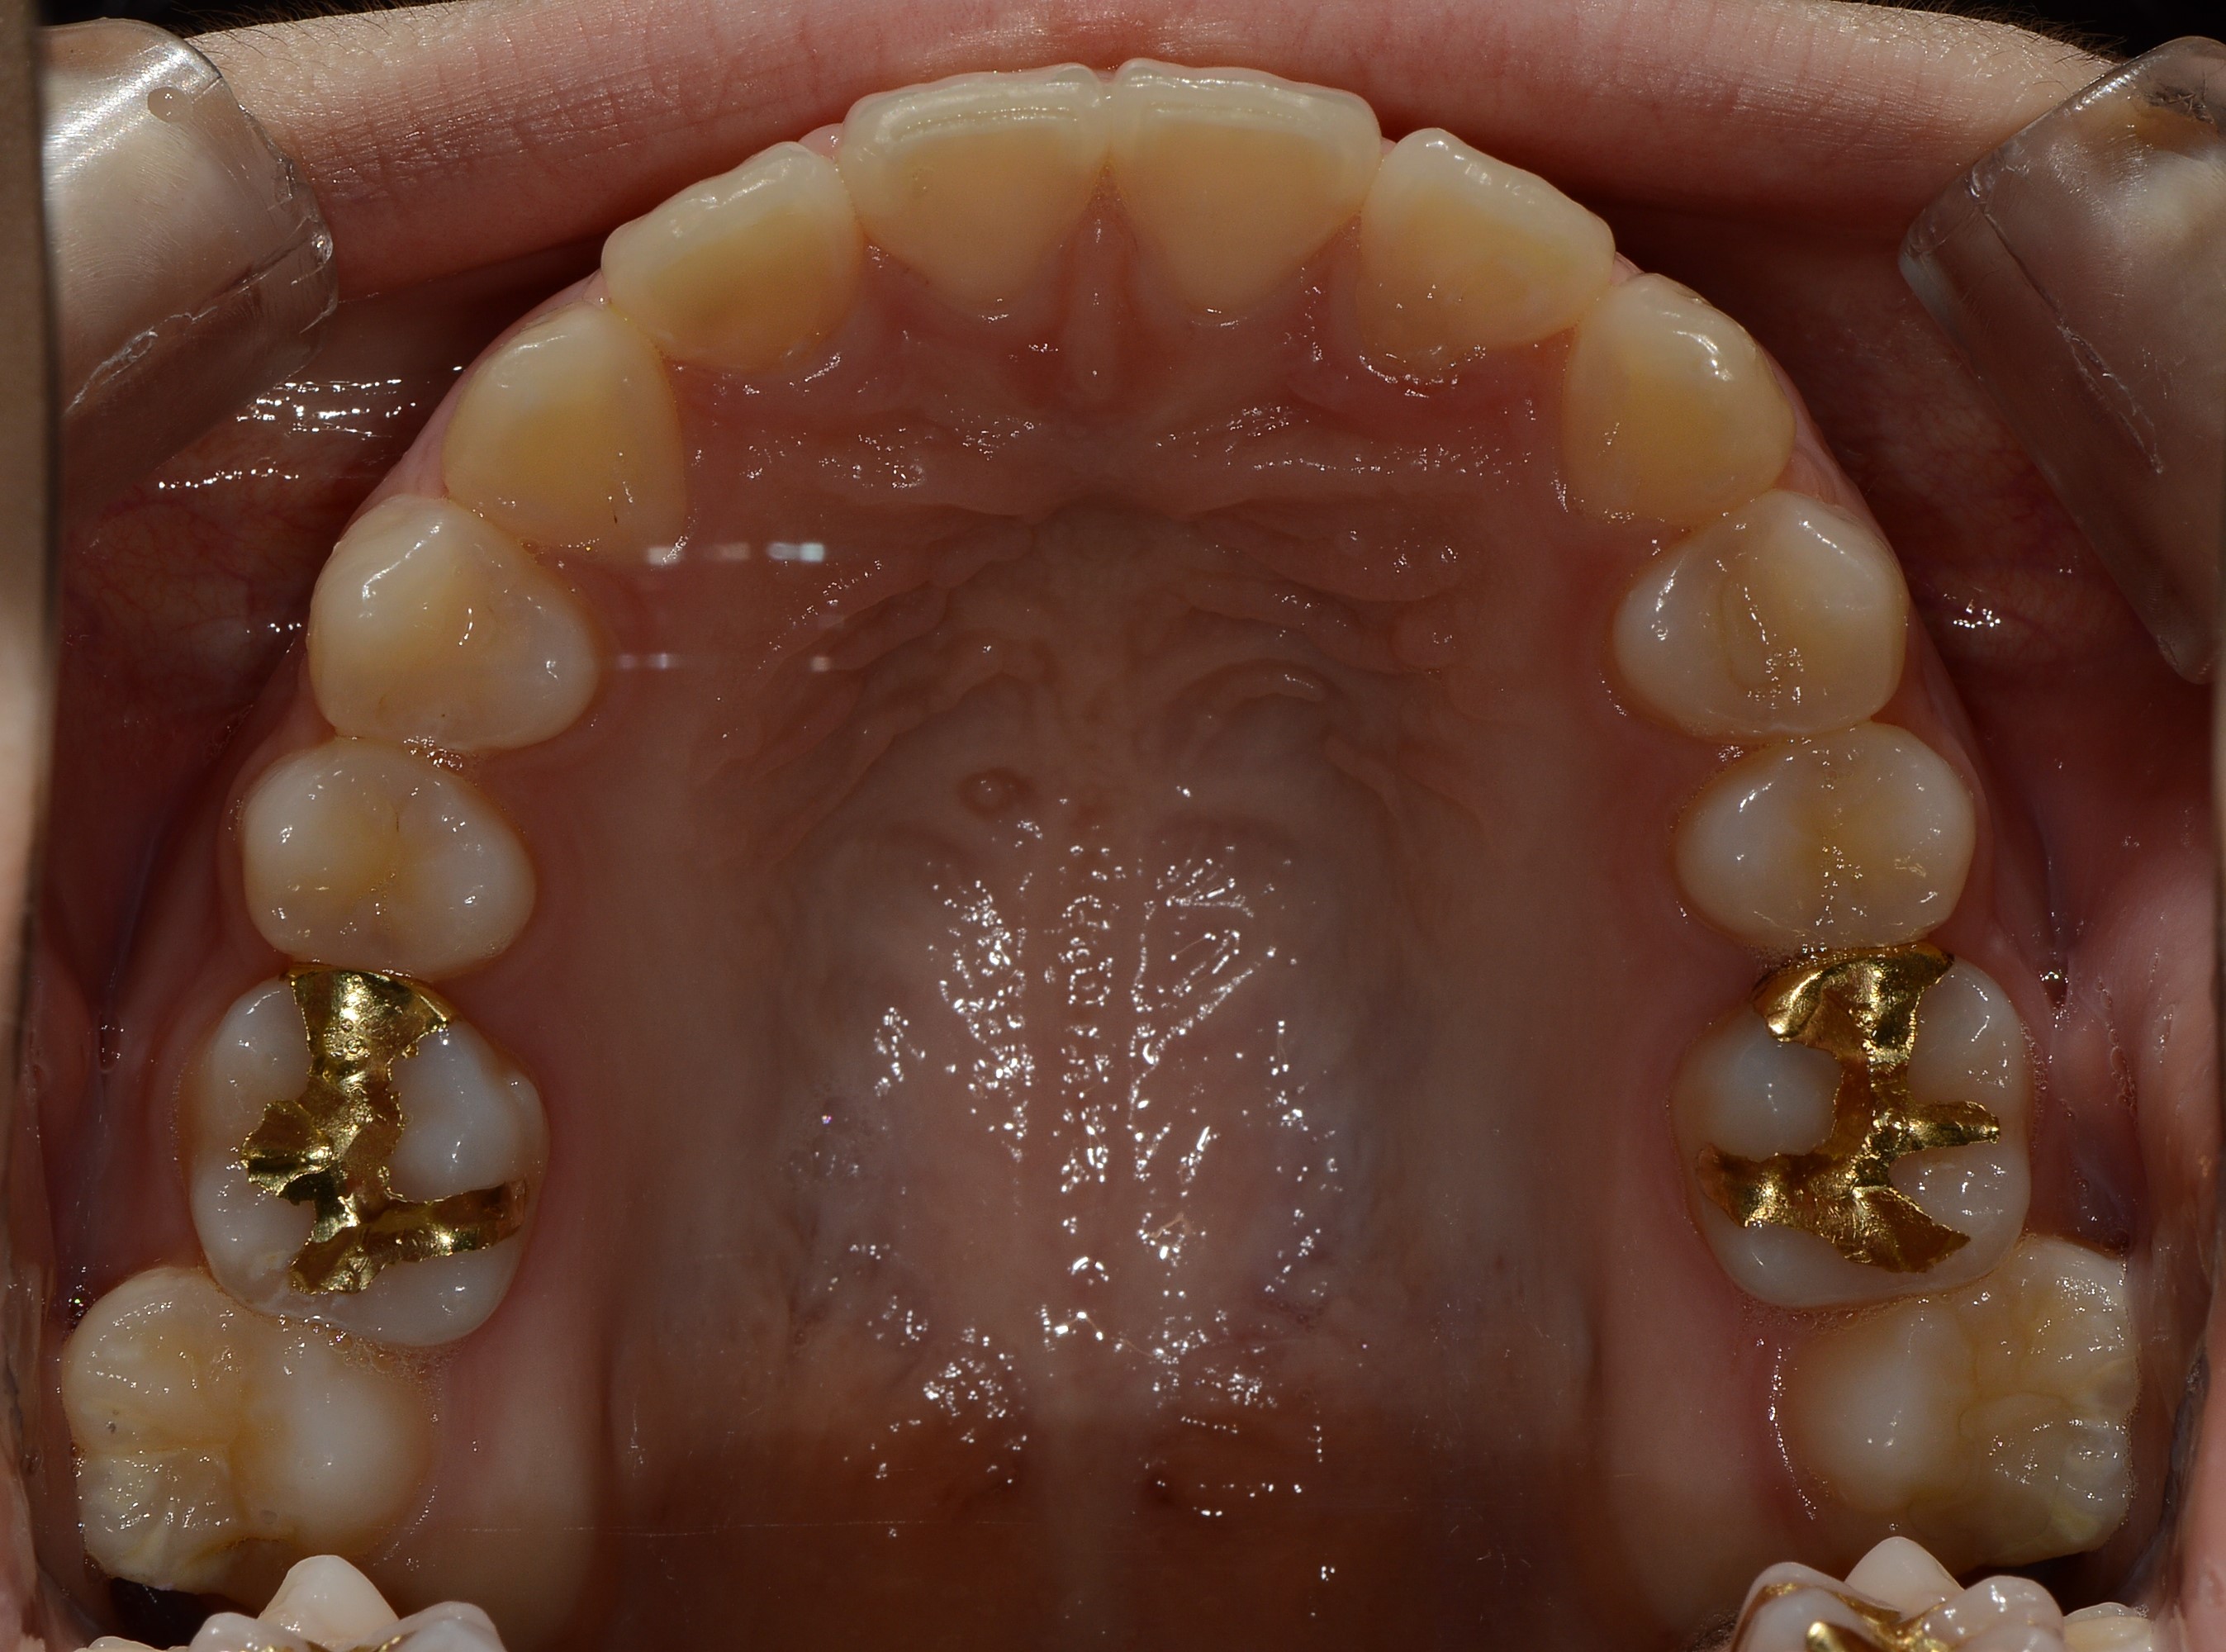

치료 후 사진입니다.